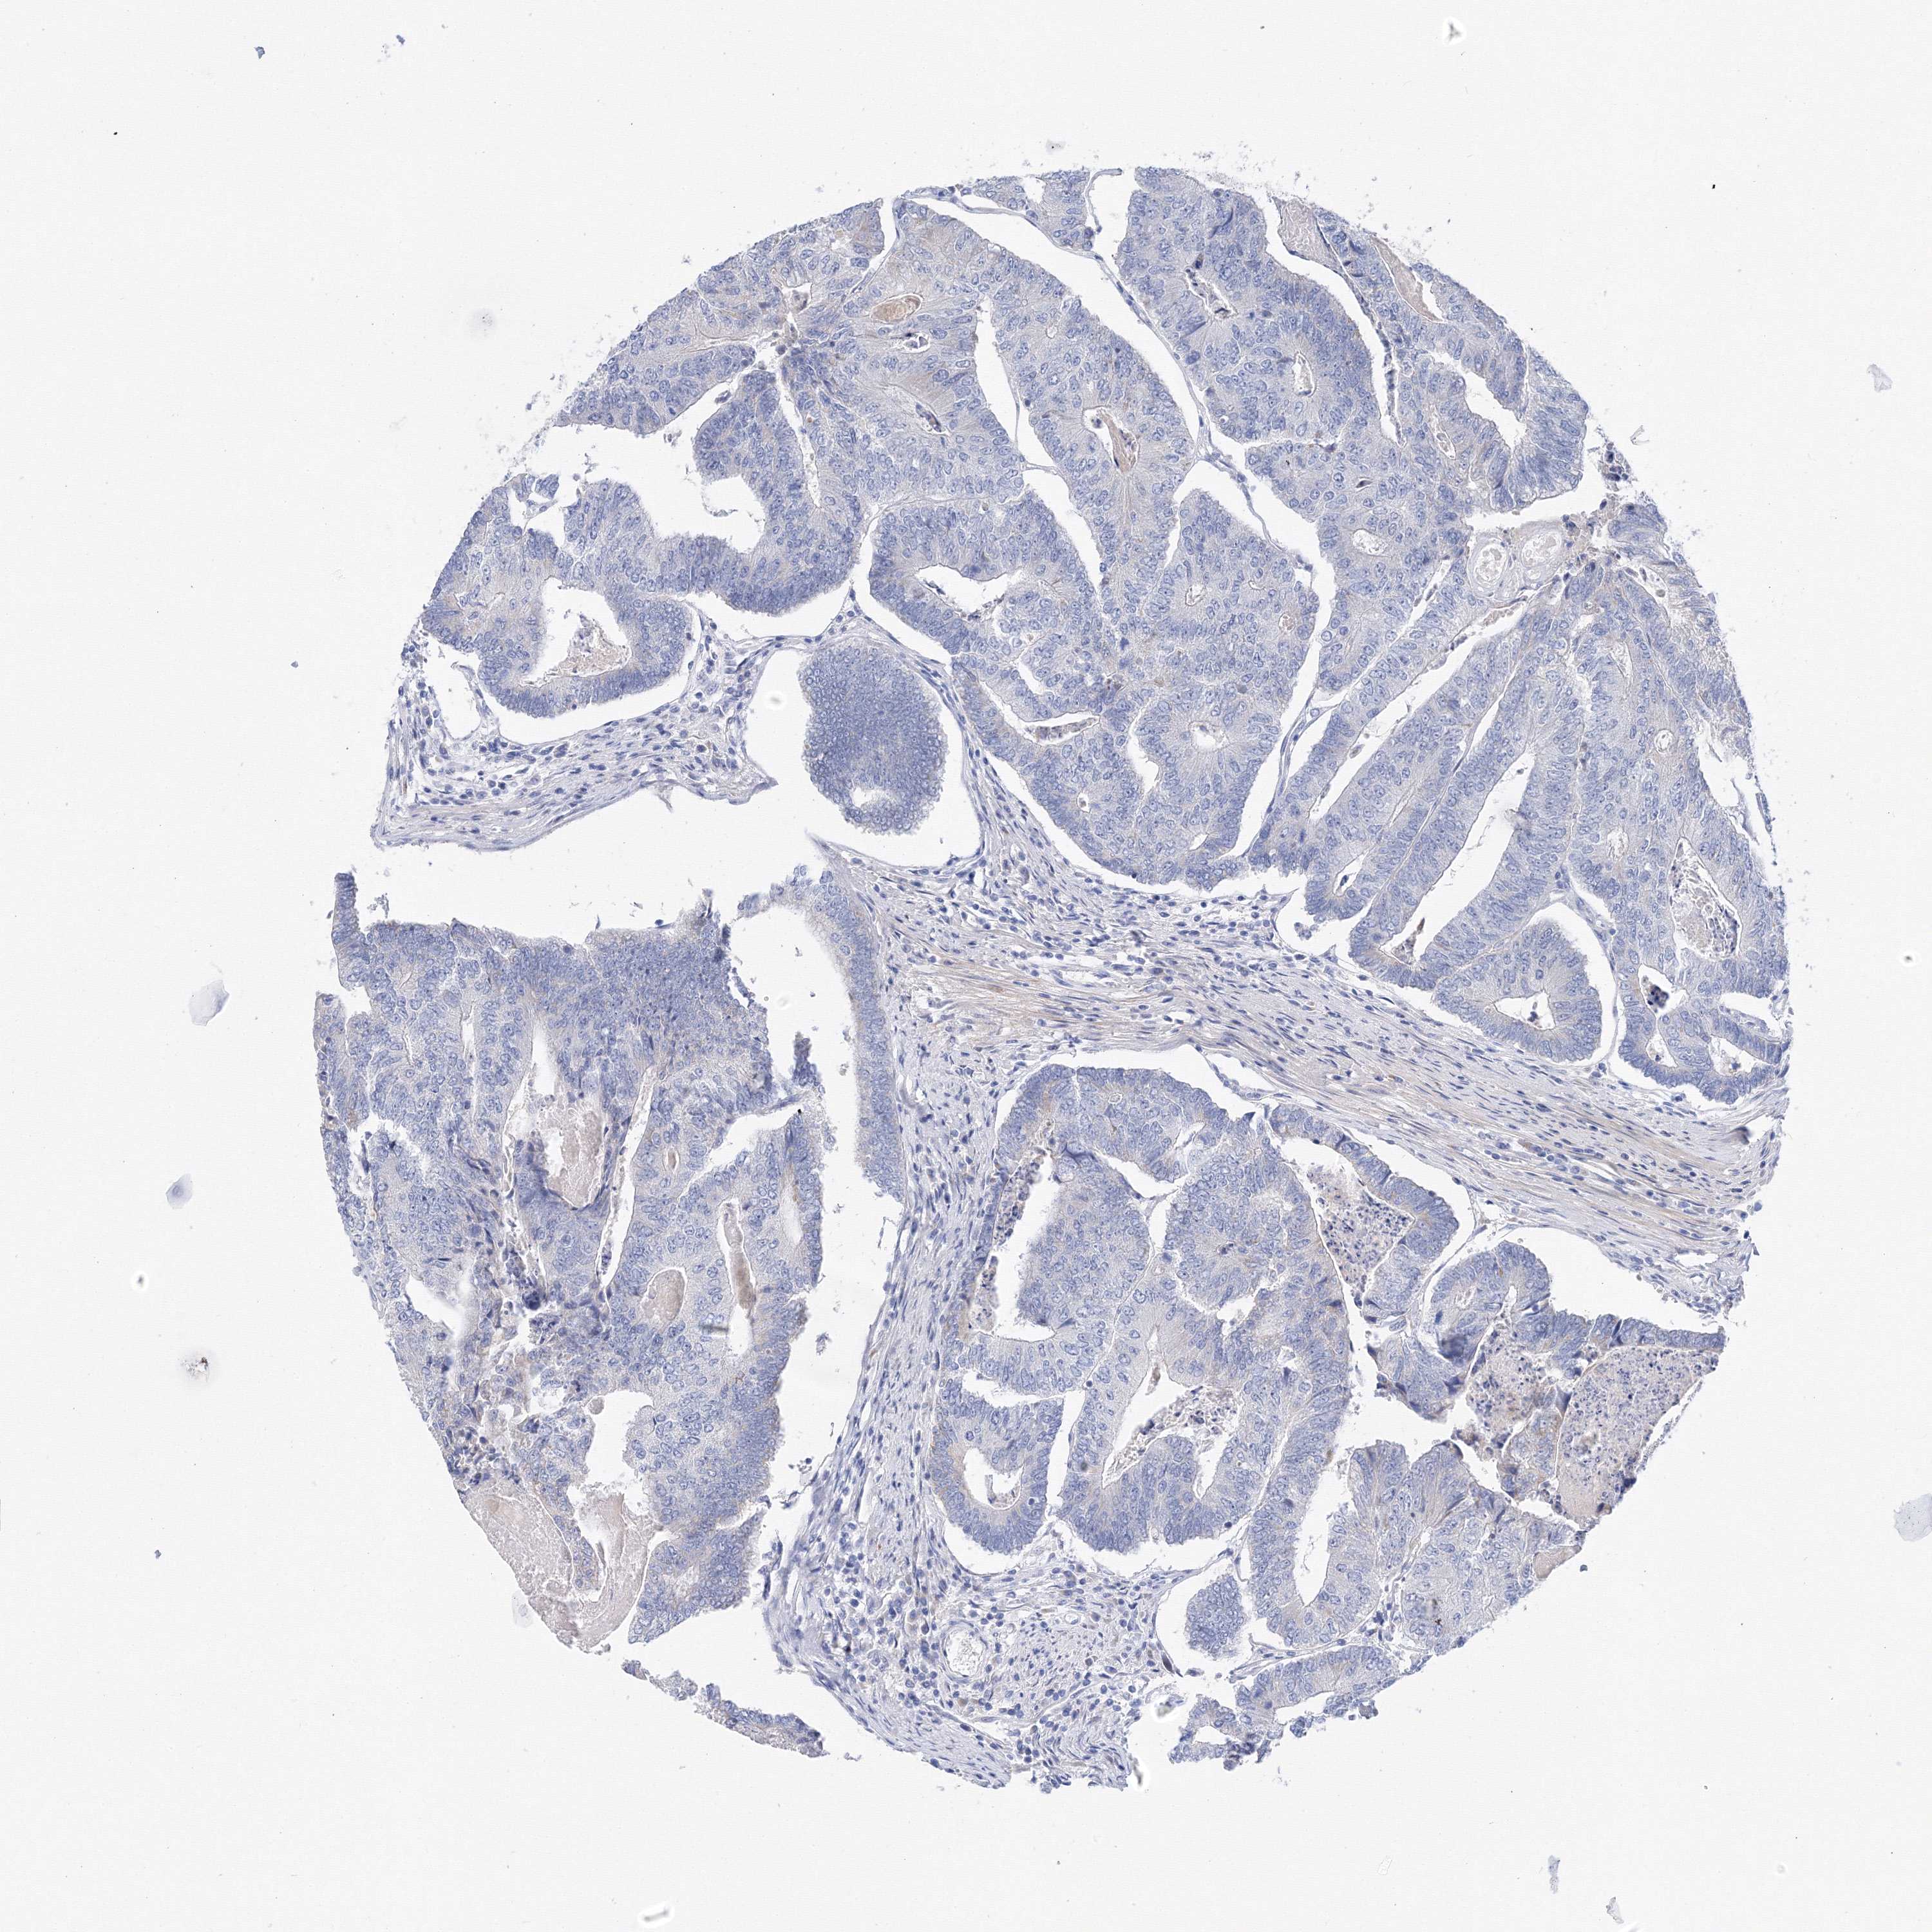

ANTIBODIES

AND

VALIDATION